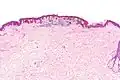

Low magnification Low magnification